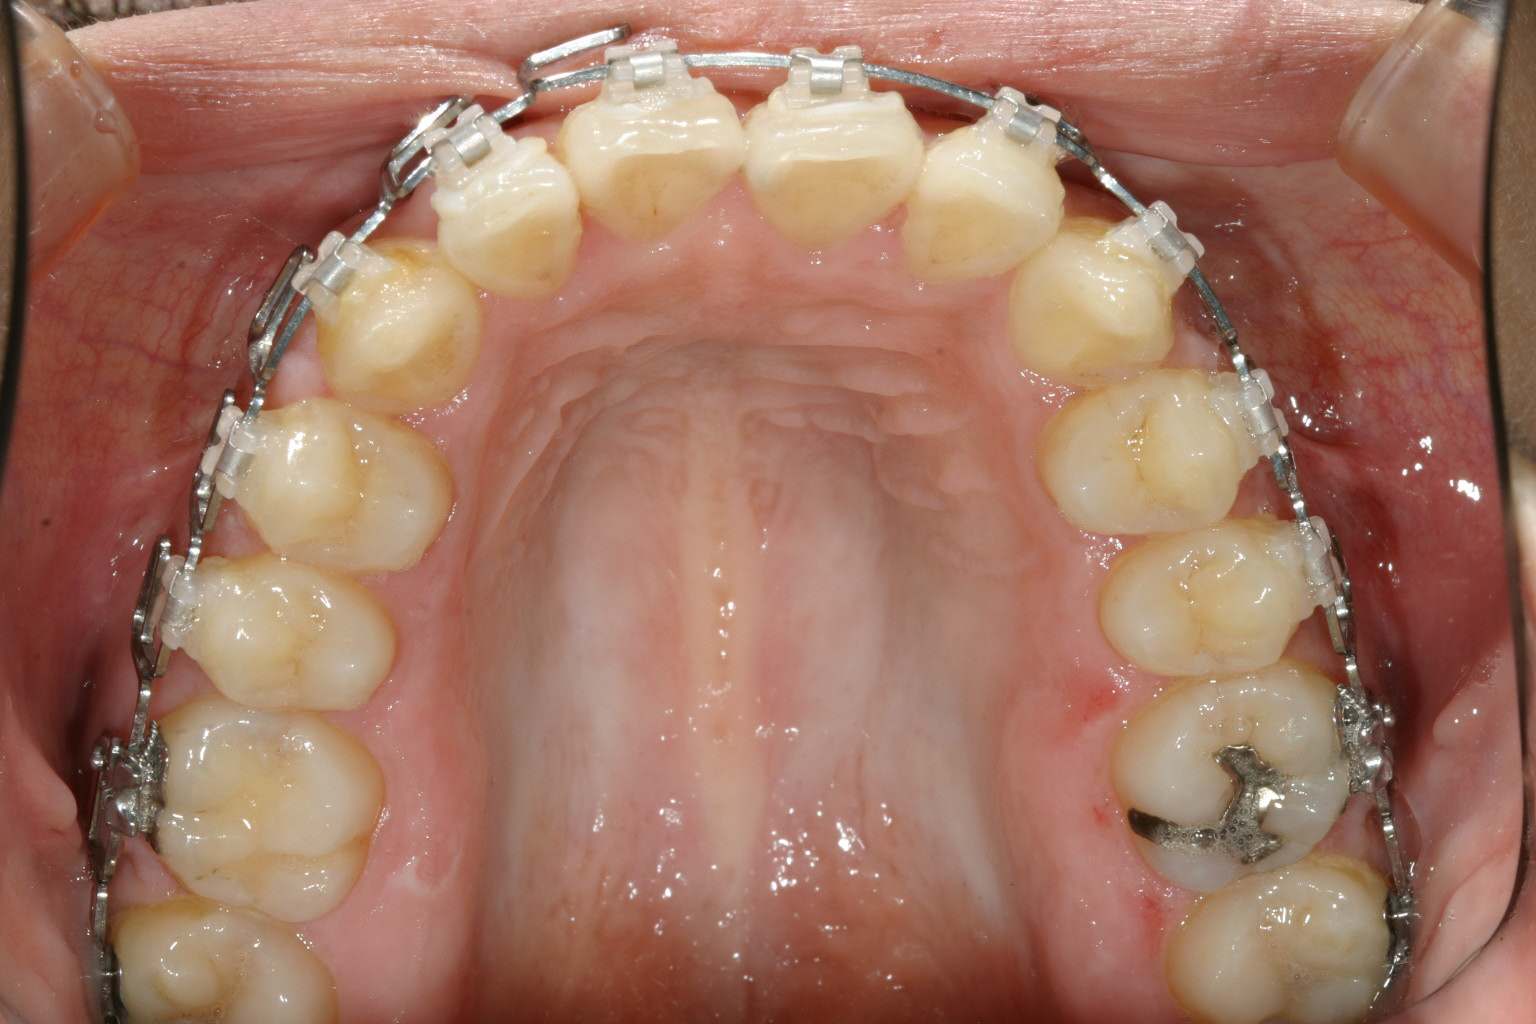

マルチループを装着5ヵ月後です。殆ど綺麗に改善しています。

下顎は殆どすでに改善しています。